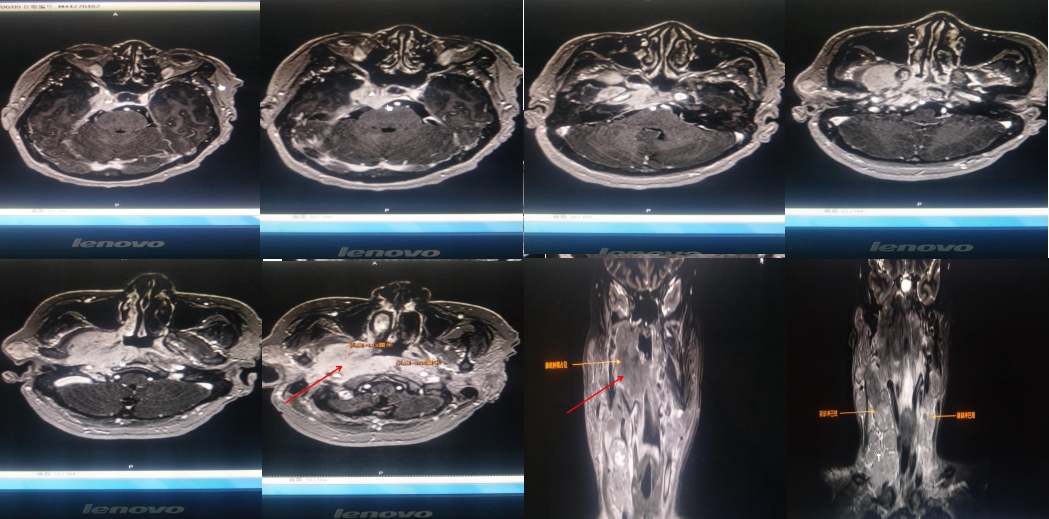

2020年6月9日我院颈部MR示:咽后壁偏右侧可见软组织影,右侧咽隐窝变窄,咽鼓管消失,病灶向外侵犯邻近软组织及颅底斜坡,包绕右侧颈内动脉,右侧翼腭窝受累,右侧腮腺受累,向左侧咽后壁延伸,颈部各区可见明显肿大淋巴结,右侧颞部脑膜受累。

横断面高信号(较白区域)为肿瘤病灶,冠状位可见明显鼻咽部肿物